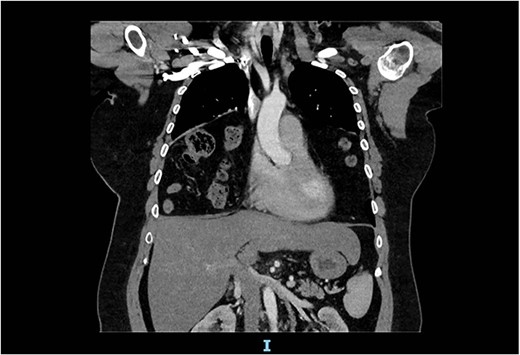

Arterial contrast CT of the chest. Coronal slice transecting the midpoint of the chest cavity showing herniation of large bowel, small bowel and omentum into the chest cavity.